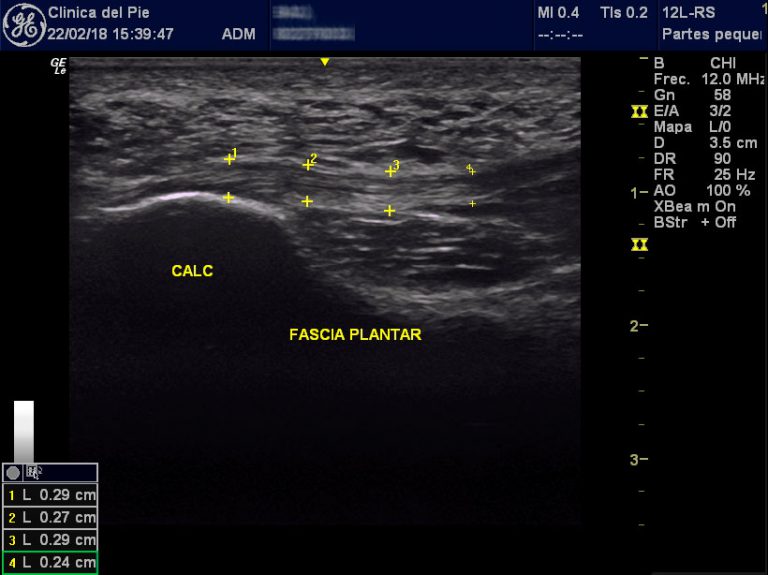

From www.clinicadelpiesegovia.com

ECOGRAFÍA Clínica del Pie Segovia Pie Equino Varo Ecografia 20 Semanas El pie equino varo describe una variedad de anomalías del pie que por lo general están presentes al momento del nacimiento. Es un trastorno congénito de las extremidades. En la ecografía en 2d de la semana 20 de embarazo se hace un estudio pormenorizado de los órganos internos del feto y de su anatomía. El pie zambo o pie equinovaro. Pie Equino Varo Ecografia 20 Semanas.